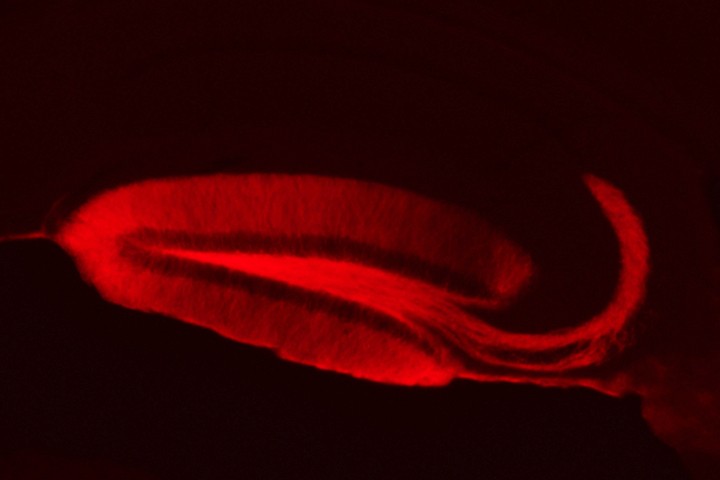

Presenilin-mediated cleavage of APP regulates synaptotagmin-7 and presynaptic plasticity. , Gael Barthet, Jordà-Siquier T, Rumi-Masante J, Bernadou F, Müller U, Mulle C